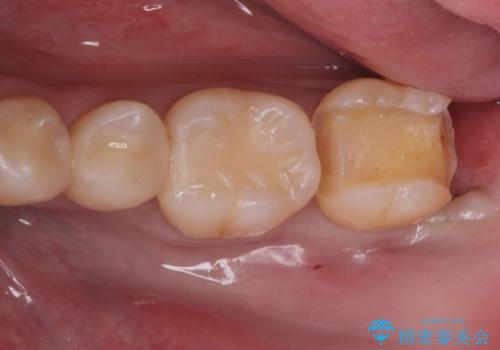

e-maxインレーによる治療

- 定期検診で来院してレントゲンを撮ったところ

歯と歯の間にう蝕ができていました。

拡大鏡下でう蝕を全て除去してe-maxインレーにて治療を行いました。

e-maxインレーは二次的にう蝕になるリスクが

銀の詰め物や樹脂の詰め物に比べて低いです。